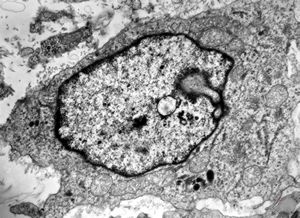

M,2y. | lymph node - lymphogranuloma - R-S cell